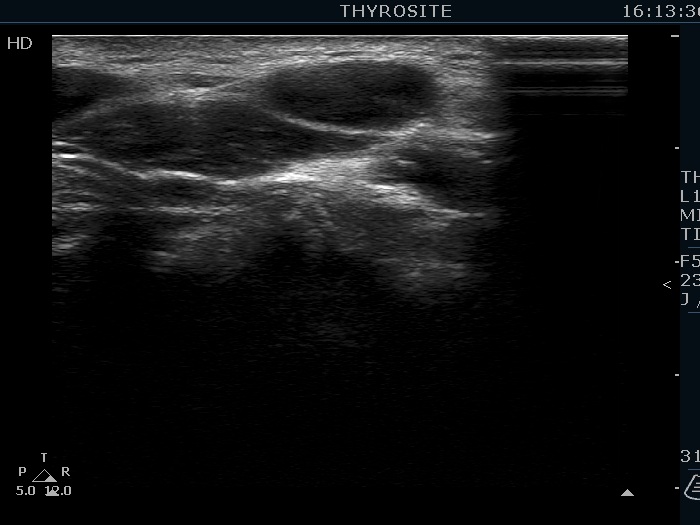

Ultrasonography. The thyroid was echonormal. There were several hypoechoic nodules in the left lobe. The middle one had back wall cystic figures. There were 3 or four discrete, deeply hypoechoic lesions above and lateral to the left lobe in the neck. One of them presented with a hilum-like figure while the others lacked hilum.